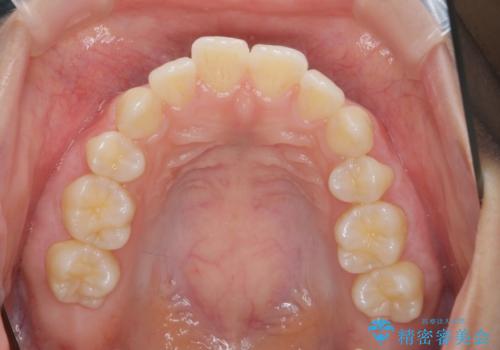

突き出た前歯の改善!マウスピースで再矯正

- 5年前にワイヤー矯正治療を終了したが、突き出たように見える前歯の仕上がりが気に入らず、再矯正治療を希望され来院されました。

マイクロインプラントを用いた遠心移動とIPRを行うことによる前歯の突出感の改善をマウスピース矯正治療で計画します。

突出していた前歯の角度が大きく改善し、審美的な仕上がりに満足いただくことができました。